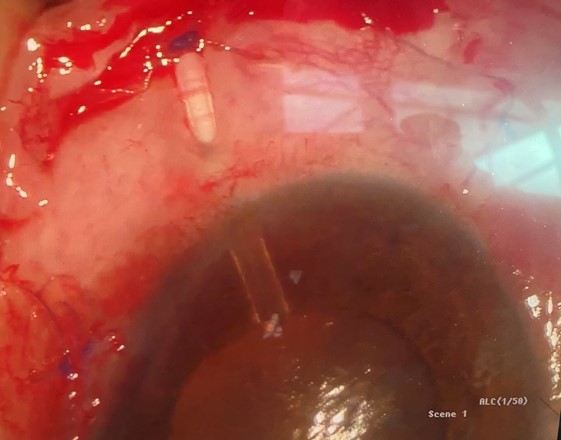

A week later, we breathed a sigh of relief to see the hyphaema had resolved and the IOP had dropped to 36mmHg… but we were totally unaware of what was coming! She walked back into the clinic with a red sore eye three days later and this time the conjunctiva overlying the plate of the Baerveldt implant had eroded, exposing the implant plate (Fig 2). The implant had to be removed urgently and we were able to offer nothing further at that stage. Hence, the fibrosed conjunctiva was sutured back in the best possible way to prevent any aqueous leak.